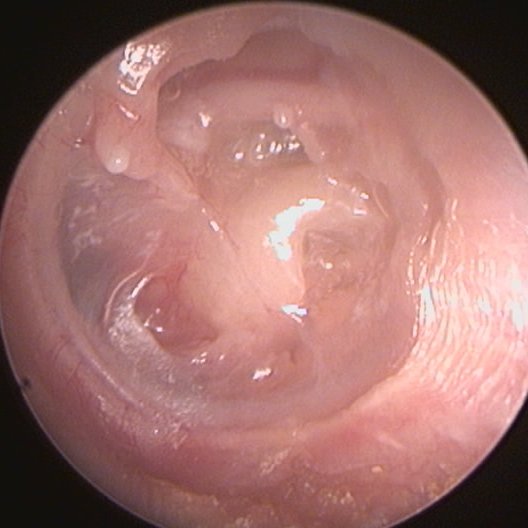

كثيرا ما تتسبب القرينيات الأنفية في معاناة مزمنة للمريض، ويعرض معاناته على عدد الأطباء، فلا تتضح لهم حقيقها، بل يظنون أن المريض يتحسس بشكل أكثر من اللازم، ويكتفون بصرف أدوية الحساسية.

والسبب هو تأثر القرينيات بوضعية المريض.

فهي تنكمش عند المشي، والوقوف وحتى الجلوس. وتتضخم عند الركوع والسجود والاستلقاء. بل إنها عند النوم تتضخم في نفس الجنب الذي ينام عليه المريض تنكمش في الجنب الآخر. وهذا التغير يحصل في يتطلب بضع دقائق.

ولهذا، عند الفحص في العيادة، لا يبدو التضخم على حقيقته.